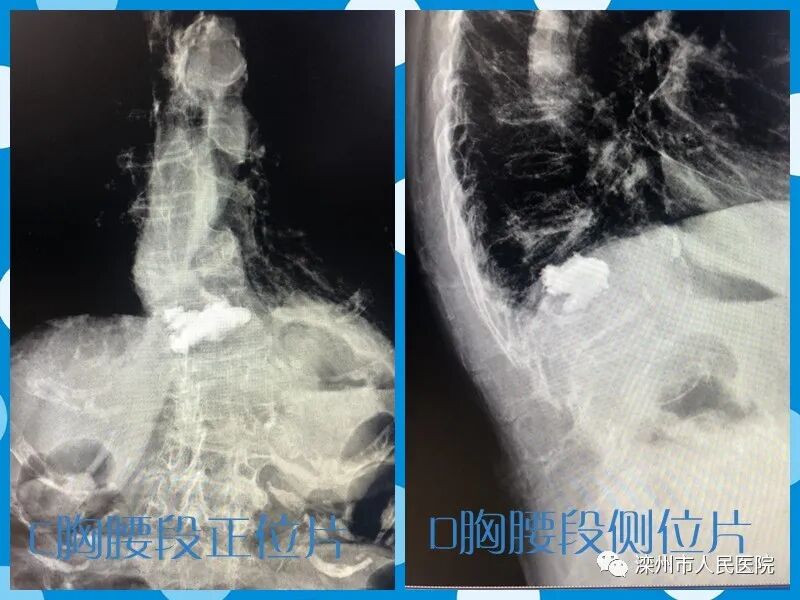

(术中影像)

(术后X线片)

秦某某

张某某